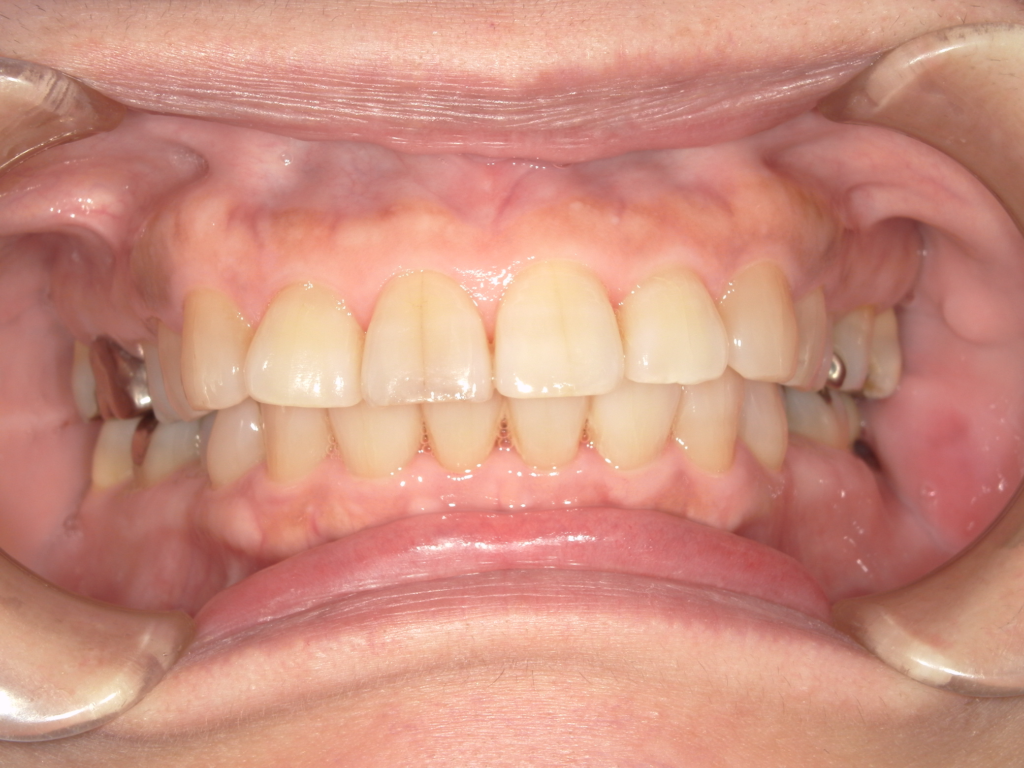

治療前

治療後